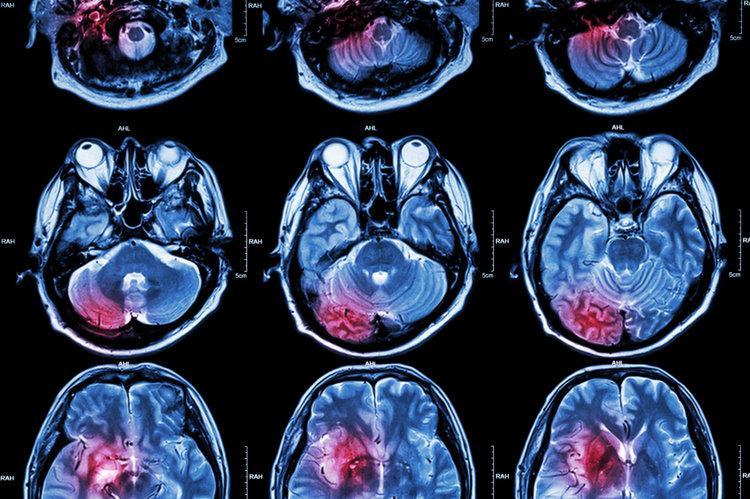

送到醫院檢查發現是腦梗死,好在送醫及時,醫生及時進行了緊急溶栓治療,避免了無可挽回的後果。

新英格蘭醫學雜誌發表的一項基於GBD2016年的研究數據顯示,1990—2016年間全世界成年人終生卒中風險可達24.9%,中國人更是位列榜首,卒中風險可達40%。另外研究發現,我國腦卒中發病率在過去20年間一直呈現上升的趨勢